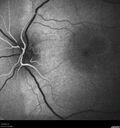

35 year old male Yesterday morning the patient woke up with poor vision in the left eye. Prior to that his vision was OK. PMHx benign. Blood pressure 154/115 mmHg. VA OD: Dcc20/16 NccJ1+ (-2) VA OS: Dcc20/40 PHNI NccJ16 IOP: TP: OD:22 OS:18 Lens clear – no uveitis Persistent fluid at 6 months required PDT laser - then fluid absorbed

Central Serous Chorioretinopathy - Expanding hot spot - photodynamic laser244 views35 year old man with acute central serous chorioretinopathy. The fluid got better then worse and the patient was treated with full strength juxtafoveal PDT and then got better.00000